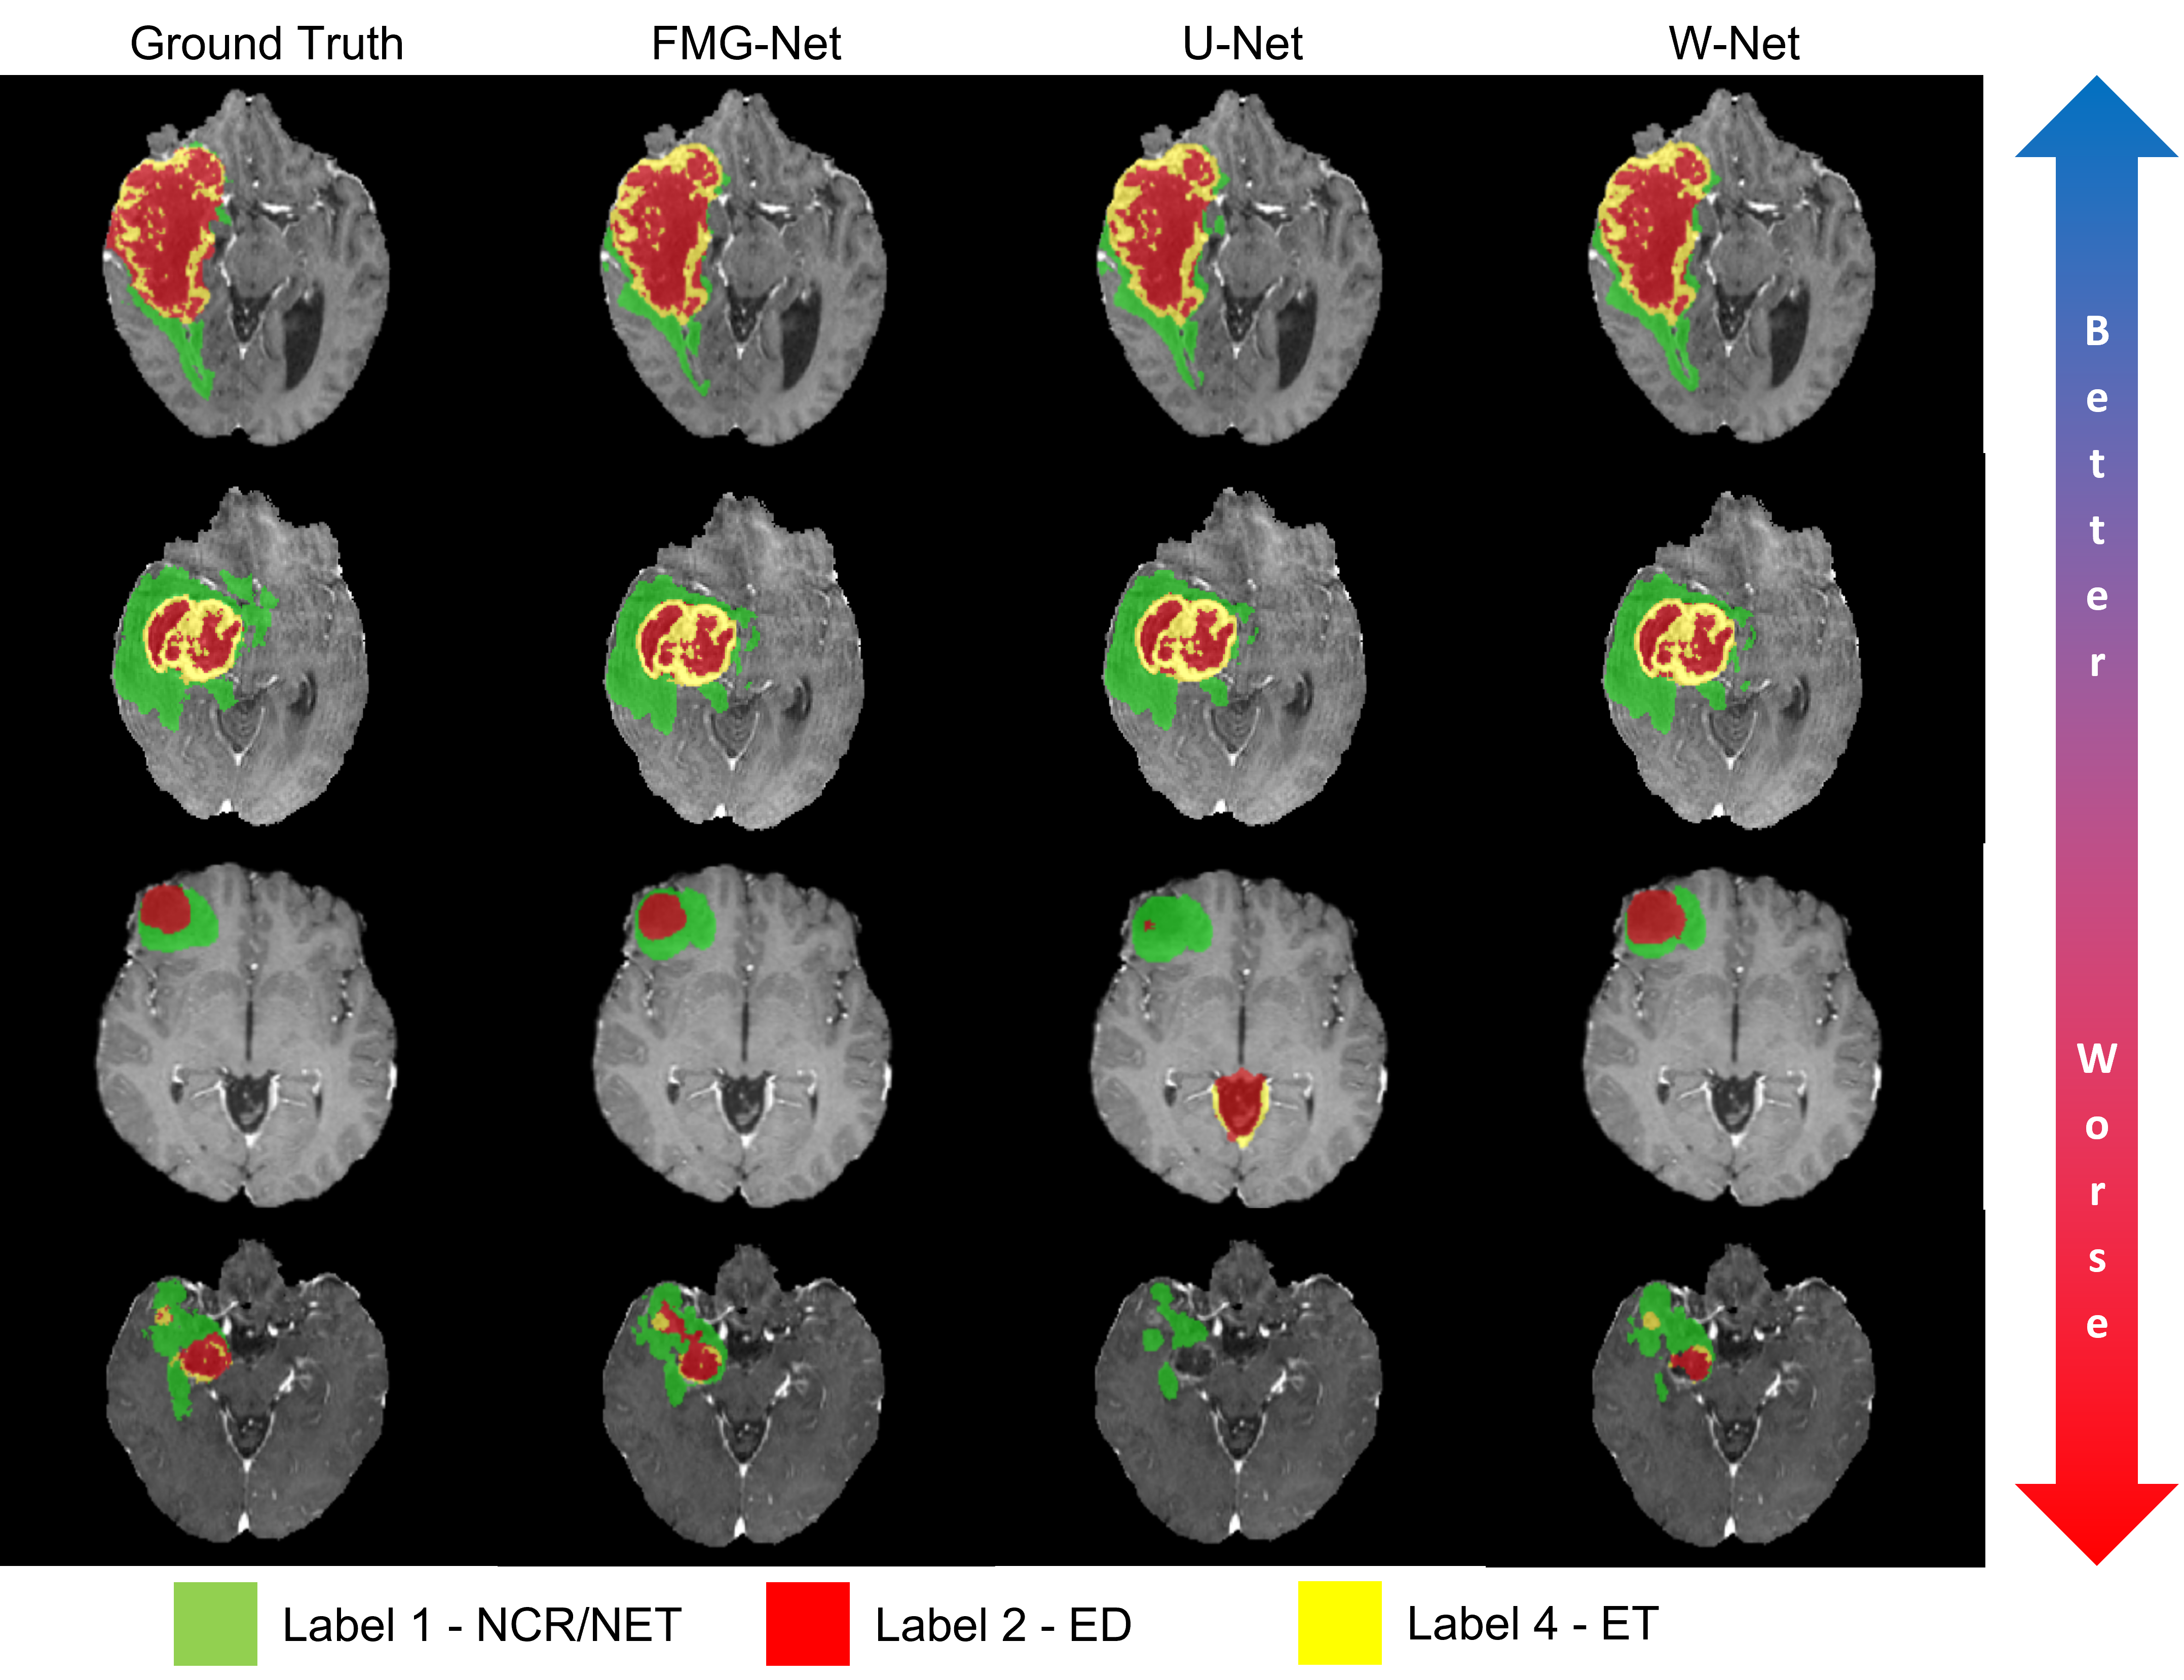

Using the methods described in Section 2, we train a 3D U-Net, FMG-Net, and W-Net and compare their segmentation performance. Table 1 shows the results for each architecture for depths 3, 4, and 5, respectively. In each case, we see that FMG-Net and W-Net generally outperform the U-Net architecture with respect to our selected metrics. Figure 4 illustrates several predictions from each of the three networks we test. Here, we see that, even for more difficult cases, the FMG-Net and W-Net can produce visually superior predictions than the U-Net.

Refer to caption

Figure 4: From left to right, ground truth and predictions from the FMG-Net, U-Net, and W-Net for several cases. Here, we see that, even for more difficult cases, the FMG-Net and W-Net can produce visually superior predictions than the U-Net.

The results presented above show that our proposed FMG and W-Net, which incorporate the design of two well-known corresponding GMM schemes, can achieve superior segmentation accuracy compared to the widely used U-Net architecture on the challenging BraTS dataset. Indeed, the proposed architectures seem to help address current CNNs’ limitations in handling multi-scale features. This ability to improve upon handling large and fine-scale features is evident in the FMG and W-Net’s superior segmentation accuracy for the various tumor subcomponents (which vary significantly in size and shape) in the BraTS dataset compared to the U-Net architecture. Figure 4 makes this clear visually, with the FMG and W-Net architectures resolving finer scale features in smaller, more difficult-to-segment tumors. However, one of the objectives of future work will be to add more comparisons to other architectures like nnUNet and HRNet (non-U-shaped) [33]. Additionally, incorporating an adaptive framework like the nnUNet (i.e., depth and network shape based on the dataset) into our architectures may improve our segmentation accuracy.